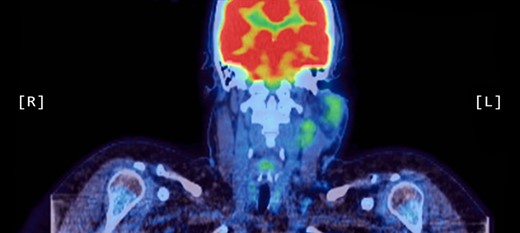

A positron emission tomography (PET) scan was subsequently arranged, which demonstrated increased uptake of the left parotid gland and several enlarged lymph nodes in the neck bilaterally (Figs 1 and 2).

Axial PET scans (A and B) showing increased uptake of the left parotid gland and enlarged left-sided lymph nodes in the neck.